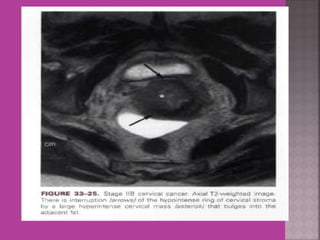

1. Cervical cancer –extent of parametrium

and pelvic organs , pelvic L.N., Endocervical.

 Gynaecological cancers--- 1. Cervical cancer –extent of parametrium and pelvic organs , pelvic L.N., Endocervical. 2.Endometrial cancer –Myometrial invasion, downward extension to cervix. 3. ovarian cancer—malignant versus benign mass, ascites , retroperitoneal node > 1cm , Bowel bladder , ano rectal . Parietal peritoneum , liver and or omental metastasis. 4. Pregnancy --- complicated by genital cancers